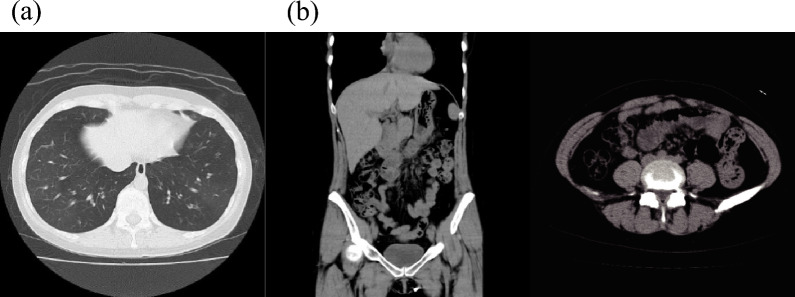

Case presentation: A 35-year-old woman who had been treated for asthma complained of worsening intermittent upper abdominal pain. Her dyspnea aggravated and she was admitted to our hospital for asthma exacerbation. Despite the improvement in her asthma symptoms with systemic corticosteroids, her abdominal pain persisted. Upper gastrointestinal endoscopic mucosal biopsy revealed eosinophilic cell infiltration; therefore, the patient was diagnosed with EoG. Dupilumab administration was initiated for asthma, while improvement of secondary EoG was expected. Following dupilumab administration, both EoG and asthma symptoms, disease control, laboratory findings, endoscopic findings, and pathological findings improved. No adverse events have been reported after the dupilumab treatment.